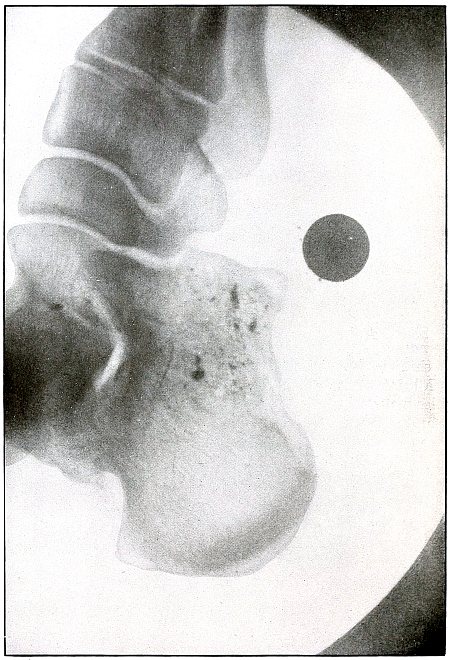

Gunshot fracture, astragalus |

310 |

| 151. |

Gunshot fracture, calcaneus |

312 |

| 152. |

Gunshot wound, heel |

314 |

| 153. |

Gunshot wound, heel |

316 |